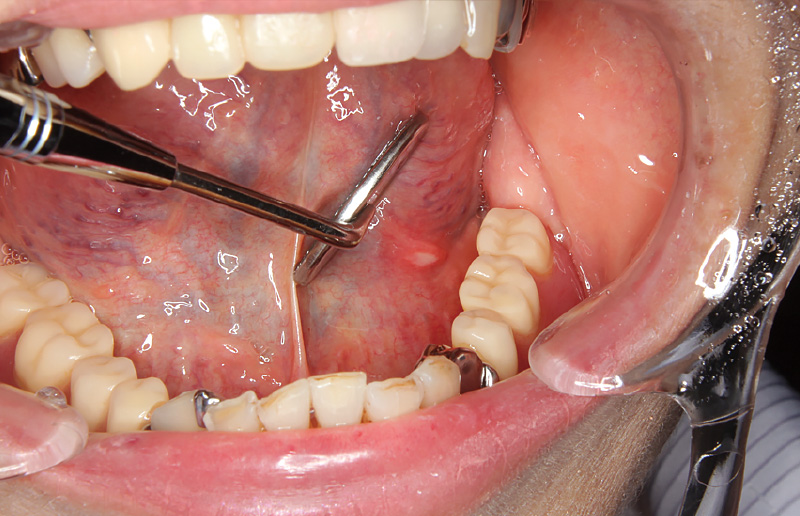

![[写真] 誤咬による舌側縁部口内炎](/academic/dentalmagazine/wp-content/uploads/sites/2/2026/04//196-8_photo06.jpg)

図6 誤咬による舌側縁部口内炎 -